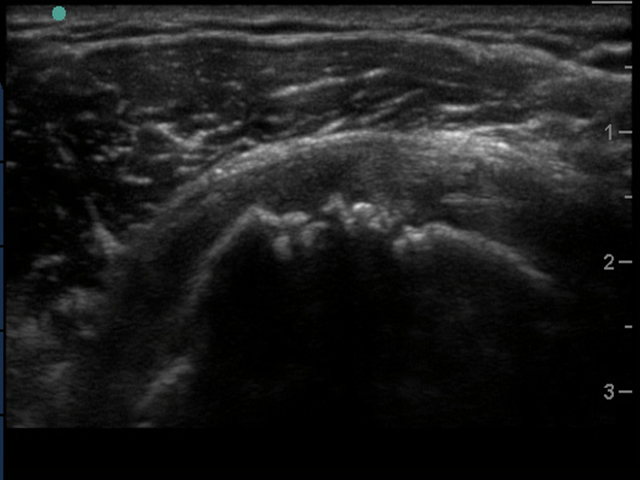

Image - Épaule : Sus-épineux, Coupe transverse, Déchirure